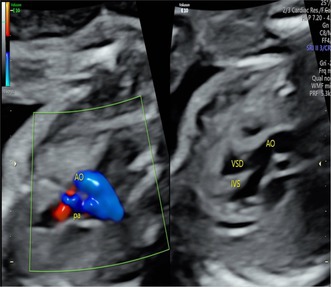

背景:法洛四联症(TOF)是最常见的紫绀型先天性心脏病。然而,我们目前对TOF的遗传病因的了解是有限的。方法:采用全外显子组测序(WES)和Sanger测序对经胎儿产前超声检查诊断为TOF的一家三口进行分析。通过基因分析来确认剪接缺陷。结果:在脑海绵状血管瘤2样(CCM2L)基因中发现了复合杂合变异体,即父本遗传无意义变异体NM_001365692.1:c。741G>A p.(Trp247Ter)和母系遗传剪接位点变异NM_001365692.1:c。1263+2T>A的TOF胎儿表现为室间隔缺损合并覆盖主动脉和肺动脉狭窄。Minigene分析显示,c.1263+2T>A变异导致CCM2L外显子8在RNA剪接过程中发生跳变,这被认为是导致移码和翻译过早终止的原因。这两种变异均未出现在公共人群数据库(Genome Aggregation Database [gnomAD]、1000 Genomes [1000G]、Clinvar)中,并根据ACMG指南(PVS1 + PM2水平证据)被归类为可能致病。结论:据我们所知,这是首次报道的人类CCM2L双等位基因功能丧失变异病例。我们的研究结果表明人类CCM2L与TOF可能存在关联。

Results: We identified compound heterozygous variants in the cerebral cavernous malformation 2-like (CCM2L) gene, namely the paternally inherited nonsense variant NM_001365692.1:c.741G>A p.(Trp247Ter) and the maternally inherited splice-site variant NM_001365692.1:c.1263+2T>A in a fetus with TOF featuring a ventricular septal defect associated with overriding aorta and pulmonary stenosis. Minigene assay showed that the c.1263+2T>A variant led to skipping of CCM2L exon8 during RNA splicing, which is thought to result in frameshift and premature termination of translation. Both variants were absent from the public population databases (Genome Aggregation Database [gnomAD], 1000 Genomes [1000G], Clinvar) and classified as likely pathogenic according to the ACMG guidelines (PVS1 + PM2 level evidence).